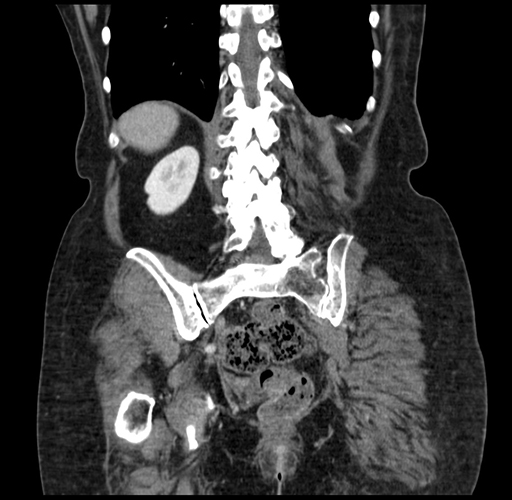

Coronal Venous